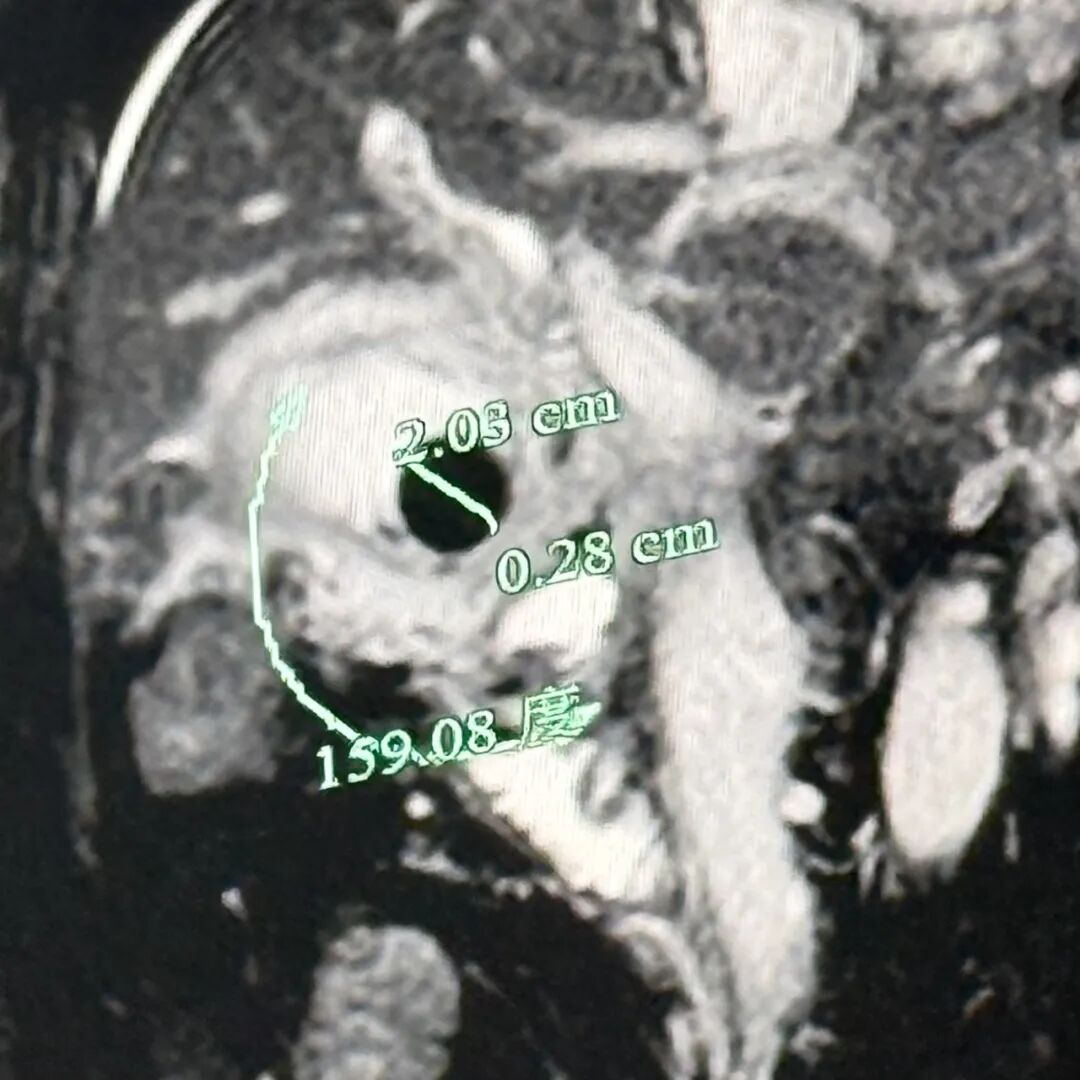

检查结果显示血常规炎症指标升高,影像提示胆囊结石、胆囊炎,胆总管、肝门部胆管、左肝胆管扩张。明确诊断为胆总管结石、胆囊结石伴急性胆囊炎

如果炎症严重且持续不缓解,胆囊会因缺血而化脓、坏疽,甚至被大网膜等周围组织粘连包裹。陈爷爷的胆囊病变已经发展到了这个阶段,这是非常危险的情况,可能导致整个腹腔的感染。

随后进行腹腔镜胆囊切除术,术中见大网膜粘连包裹胆囊,胆囊已化脓坏疽,大小约12cm×8cm×6cm,手术团队仔细钝性分离粘连,小心避开周围组织血管,完整切除了病变胆囊。

“陈爷爷长期患有胆囊结石,反复引发胆囊炎致腹部疼痛,后结石落入胆总管造成了胆总管梗阻,引起了更剧烈的疼痛,并导致了胆管和肝内胆管的扩张,最终造成了胆囊大面积化脓坏疽、炎症包裹的严重后果。”